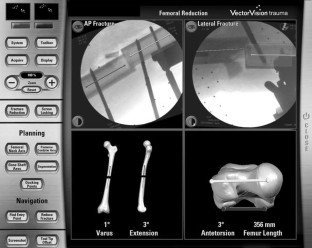

Fig. 1